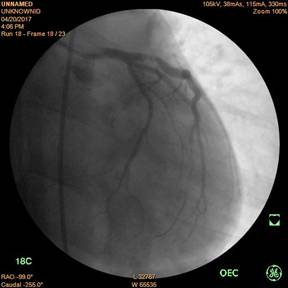

Động mạch vành trái trước và sau khi đặt stent

Bệnh nhân tên là Võ Hữu T., 30 tuổi, ở Phú Lộc, tiền sử hút thuốc lá và uống rượu nhiều. Bệnh khởi phát cách nhập viện 10 ngày với biểu hiện sốt, đau họng, ho, đau ngực sau xương ức tăng lên khi ho, đau ngực khi gắng sức. Các xét nghiệm cho thấy có hội chứng nhiễm trùng và tăng men tim, có dấu chứng tổn thương tim trên điện tâm đồ, làm siêu âm tim cấp cứu với kết quả giảm vận động buồng tim, chức năng tim giảm, được hội chẩn khẩn. Với quyết định chụp và can thiệp khẩn trương, bệnh nhân đã được nong và đặt stent động mạch vành trái.

Ngay sau đặt stent động mạch vành, bệnh nhân giảm đau ngực nhiều, men tim giảm, cảm giác khoẻ hơn.